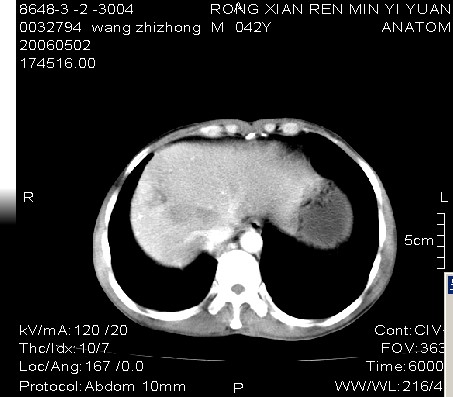

男:42岁。反复恶心呕吐半年。b超:右肝内多发占位,胆石胆囊炎.胆总管扩张

本例特点动脉期右叶近肝门区可见高密度强化,后段也见早期强化,静脉期肝门区高密度区造影剂退出,余密度均匀,考虑肝癌伴动静脉漏,肝右叶上段可见扩张胆管,考虑由于肿瘤压迫胆管引起阻塞,

8楼战友的分析很到位。我刚才在科室中从与患者的爱人交谈中得之。患者近半年来反复恶心呕吐,常伴有右上腹痛及间隙性皮肤黄染,不能吃油脂类食物,否则要腹泻。在作ct时患者家属隐瞒了患者有乙肝,及afp病史.{由于患者家离城较远.拒绝平扫检查}.谢谢各位战友的讨论!!